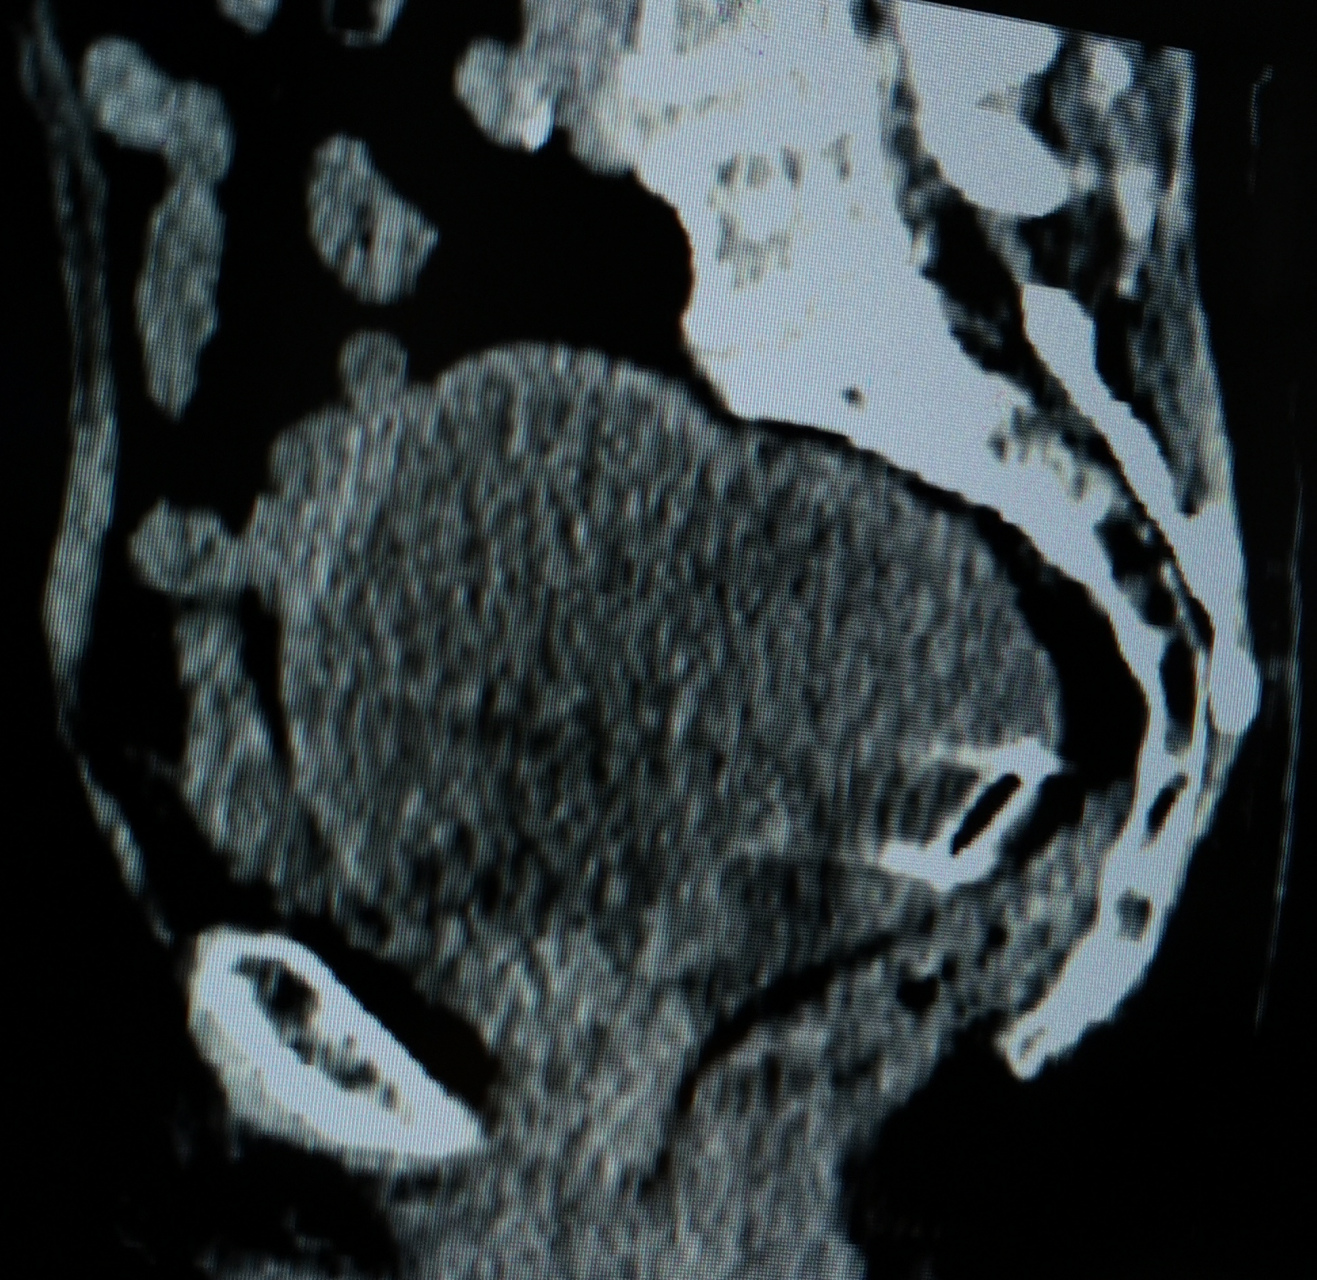

宫腔大量积液,积脓 老年女性,75岁,下腹痛做盆腔ct,子宫增大呈球形

图片尺寸1317x1280